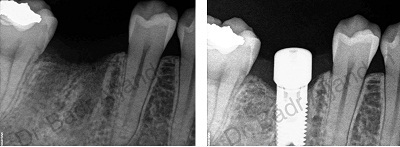

The implants themselves are tiny titanium posts, which are inserted into the jawbone where teeth are missing. These metal anchors act as tooth root substitutes. They are surgically placed into the jawbone. The bone bonds with the titanium, creating a strong foundation for artificial teeth. Small posts are then attached to the implant, which protrude through the gums. These posts provide stable anchors for artificial replacement teeth.

For most patients, the placement of dental implants involves two surgical procedures. First, implants are placed within your jawbone. For the first three to six months following surgery, the implants are beneath the surface of the gums gradually bonding with the jawbone. You should be able to wear temporary dentures and eat a soft diet during this time. At the same time, your dentist is forming new replacement teeth.

After the implant has bonded to the jawbone, the second phase begins. Dr. Al-jandan will uncover the implants and attach small posts that protrude through the gums and will act as anchors for the artificial teeth. When the artificial teeth are placed, these posts will not be seen. The entire procedure usually takes six to eight months. Most patients experience minimal disruption in their daily life.

Using the most recent advances in dental implant technology, Dr.Al-jandan is able to place single stage implants. These implants do not require a second procedure to uncover them, but do require a minimum of six weeks of healing time before artificial teeth are placed. There are even situations where the implants can be placed at the same time as a tooth extraction – further minimizing the number of surgical procedures.